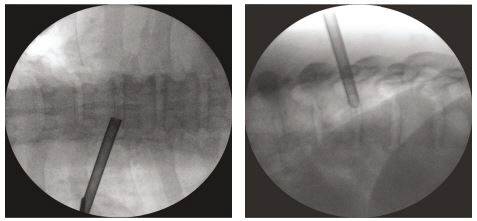

흉추 디스크 내시경 수술은 2000년 우리들병원이 개발 정립한 이후 임상 연구와 논문 발표, 국제 학회 강연 등을 통해 안전성과 우수한 치료 효과를 인정받으면서 국내외 척추 전문의들이 활발하게 배우고 있는 고난도 척추 수술법이다. 흉추 정 중앙에서 6~7cm 지점을 0.5mm 정도 최소 절개한 후 흉추 내시경을 이용해 척추 사이의 공간인 추간공으로 접근, 영상 화면을 보면서 탈출된 디스크를 레이저와 고주파로 정밀하게 제거하는 최첨단 기술이다.

논문에 따르면, 전통적인 개방형 흉추 수술은 흉추 중앙의 척추 후궁이나 척추 후관절, 흉추 측면의 늑골 횡돌기 등으로 접근하는 절개 수술로 전신마취가 필요하고, 신경을 벌리거나 뼈를 자르는 등 수술 부위가 크기 때문에 수술 후 신경 및 혈관 손상, 하반신 마비 등의 합병증 발생률이 약 25%로 보고되고 있다. 이와 달리 전신마취 없이 최소 절개로 내시경을 이용해 흉추관 사이의 공간(추간공)으로 접근하면 뼈, 신경, 근육 등 정상적인 구조물들을 전혀 손상시키지 않고 신경을 압박하고 있는 디스크만을 정확하게 제거할 수 있기 때문에 합병증의 위험없이 안전하고 효과적이다.

이때 사용하는 내시경은 우리들병원이 세계 최초로 흉추에 적합하도록 개발한 것으로 디스크 탈출증, 흉추관 협착증 등에 널리 활용되고 있다. 국소마취 하에서 최소침습 치료가 가능하기 때문에 척추 신경을 건드리거나 정상조직을 손상시키지 않아 안전하며 입원기간이 짧고 회복이 빠르다. 흉추수술의 위험성으로 수술을 포기한 채 10년, 20년 통증을 안고 살아가는 많은 환자들에게 치료 가능성이 열렸다.